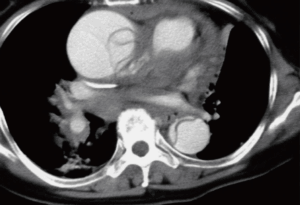

・CT検査(造影CT) : 血管がどこからどこまで裂けているのか、緊急手術が必要かを判断します。CT検査が診断には必須になります。